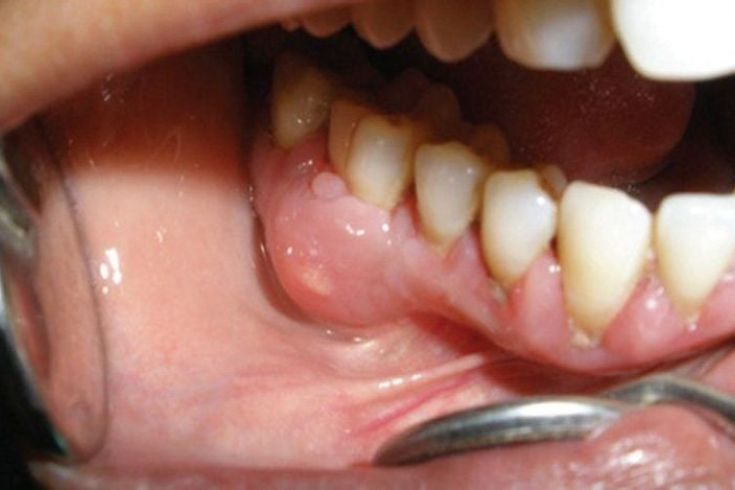

Áp xe trong miệng là một dạng viêm nhiễm cấp tính trong nha khoa, xảy ra khi vi khuẩn xâm nhập sâu vào tủy răng hoặc mô quanh chân răng, dẫn đến hiện tượng tích tụ mủ. Ổ mủ hình thành khi hệ miễn dịch sản xuất bạch cầu để phản ứng với vi khuẩn xâm nhập, khiến khu vực nhiễm trùng sưng to, đau nhức và có thể gây ra mùi hôi khó chịu. Áp xe thường do vi khuẩn xâm nhập vào tủy răng qua lỗ sâu không được điều trị, hoặc có thể bắt nguồn từ viêm nha chu, sâu răng, hoặc điều trị tủy không triệt để. Ngoài ra, vệ sinh răng miệng kém cũng tạo điều kiện cho vi khuẩn phát triển và gây nhiễm trùng.

Áp xe nướu: Áp xe nướu xảy ra ở mô nướu, thường do thức ăn thừa hoặc dị vật kẹt giữa nướu và răng gây viêm cấp tính. Loại này thường thấy ở những người có thói quen vệ sinh răng miệng kém.

Nướu sưng đỏ: Vùng nướu bị viêm có thể nổi mủ.